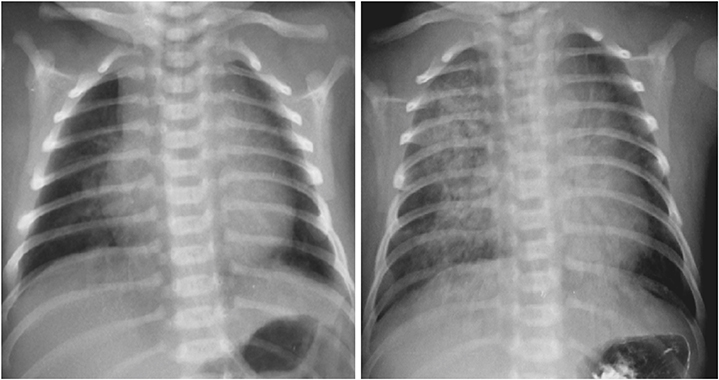

A male full-term neonate presented to emergency room with cyanosis after breastfeeding. The patient was delivered by planned caesarian section 12 hours before arrival. Chest radiograph taken on the first day of life was cleaned but the radiograph taken on the third day of life suggested aspiration pneumonitis (

Fig. 1). Upper gastrointestinal (GI) series showed gastroesophageal regurgitation with pulmonary aspiration but esophagoscopy and video esophagogram on the eleventh day of life showed no abnormality. Contrast esophagogram was followed on the 33

Fig. 1 Two days after birth (right), chest radiograph shows aspiration pneumonitis which was absent on the date of birth (left).